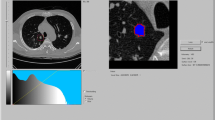

There was, however, a significant difference in absolute nodule volumes among software packages. This can lead to variations in management decisions: Software X and Y will measure higher volume (and thus, effective diameter) than software Z, for example, and will therefore induce more aggressive management decisions if recommendations by the Fleischner society are followed. [6]. Consequently, the nodule shown in Fig. 5 would be treated differently depending on the segmentation algorithm used. As shown in Table 2, the size changes required to detect significant growth may be substantially greater when different software packages are used for baseline and follow-up evaluation instead of the same package for both examinations. In addition, there is a substantial bias, which means that the systematic differences in mean volumes can lead to a situation in which a growing nodule will appear to have shrunk (e.g., first measurement with software F, second measurement with software E) or a stable nodule will appear to have grown (e.g., first measurement with software E, second measurement with software F).